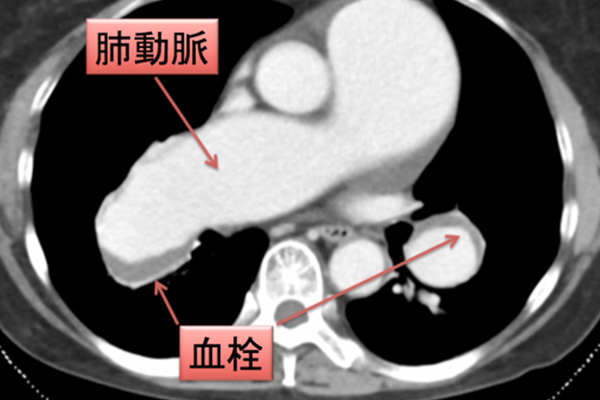

単一の血栓が複数の塞栓症を引き起こす可能性があります。破片が剥がれて体の他の部分に詰まる可能性があります。一部の塞栓は脳、心臓、肺、腎臓に移動します。

動脈が詰まると、患部の組織損傷や死を引き起こす可能性があります。このため、動脈塞栓症は医療上の緊急事態です。永久的な損傷を防ぐためには、直ちに治療する必要があります。

- MRI — 体の画像を撮影して血栓の位置を特定します